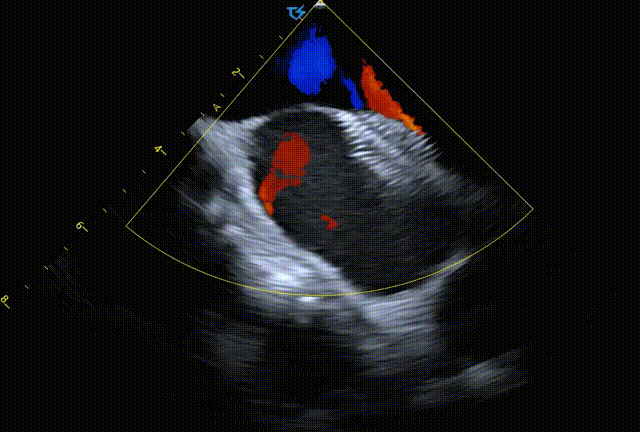

图3 霆升ICE直视下膜周部室间隔缺损封堵

从诊断的角度出发,在解剖方面心腔内超声(ICE)可以精确诊断缺损特征,更准确地显示室间隔缺损的大小、位置、形态以及与周围结构的关系,为治疗方案地指定提供更强有力的证据,血流动力学方面,ICE可以更准确地评估血流速度和分流方向,有助于评估缺损对心脏功能地影响。而从治疗的角度出发,在房间隔缺损封堵术中,ICE能够在封堵器释放前后在不同切面上准确测量房间隔缺损直径,评估缺损边缘的长度和厚度,这些均有助于选择合适尺寸的封堵器,确保封堵器紧密贴合残损边缘,避免残余分流。在复杂或特殊类型的室间隔缺损中,ICE的诊断更准确,引导效率更高,极大地提高了封堵手术的成功率。同时ICE可以更好的避免如心包积液、封堵器移位等术中并发症的发生。与传统的X线透视引导相比,ICE减低了医患的辐射暴露,并减少了造影剂过敏、肾损伤等风险。